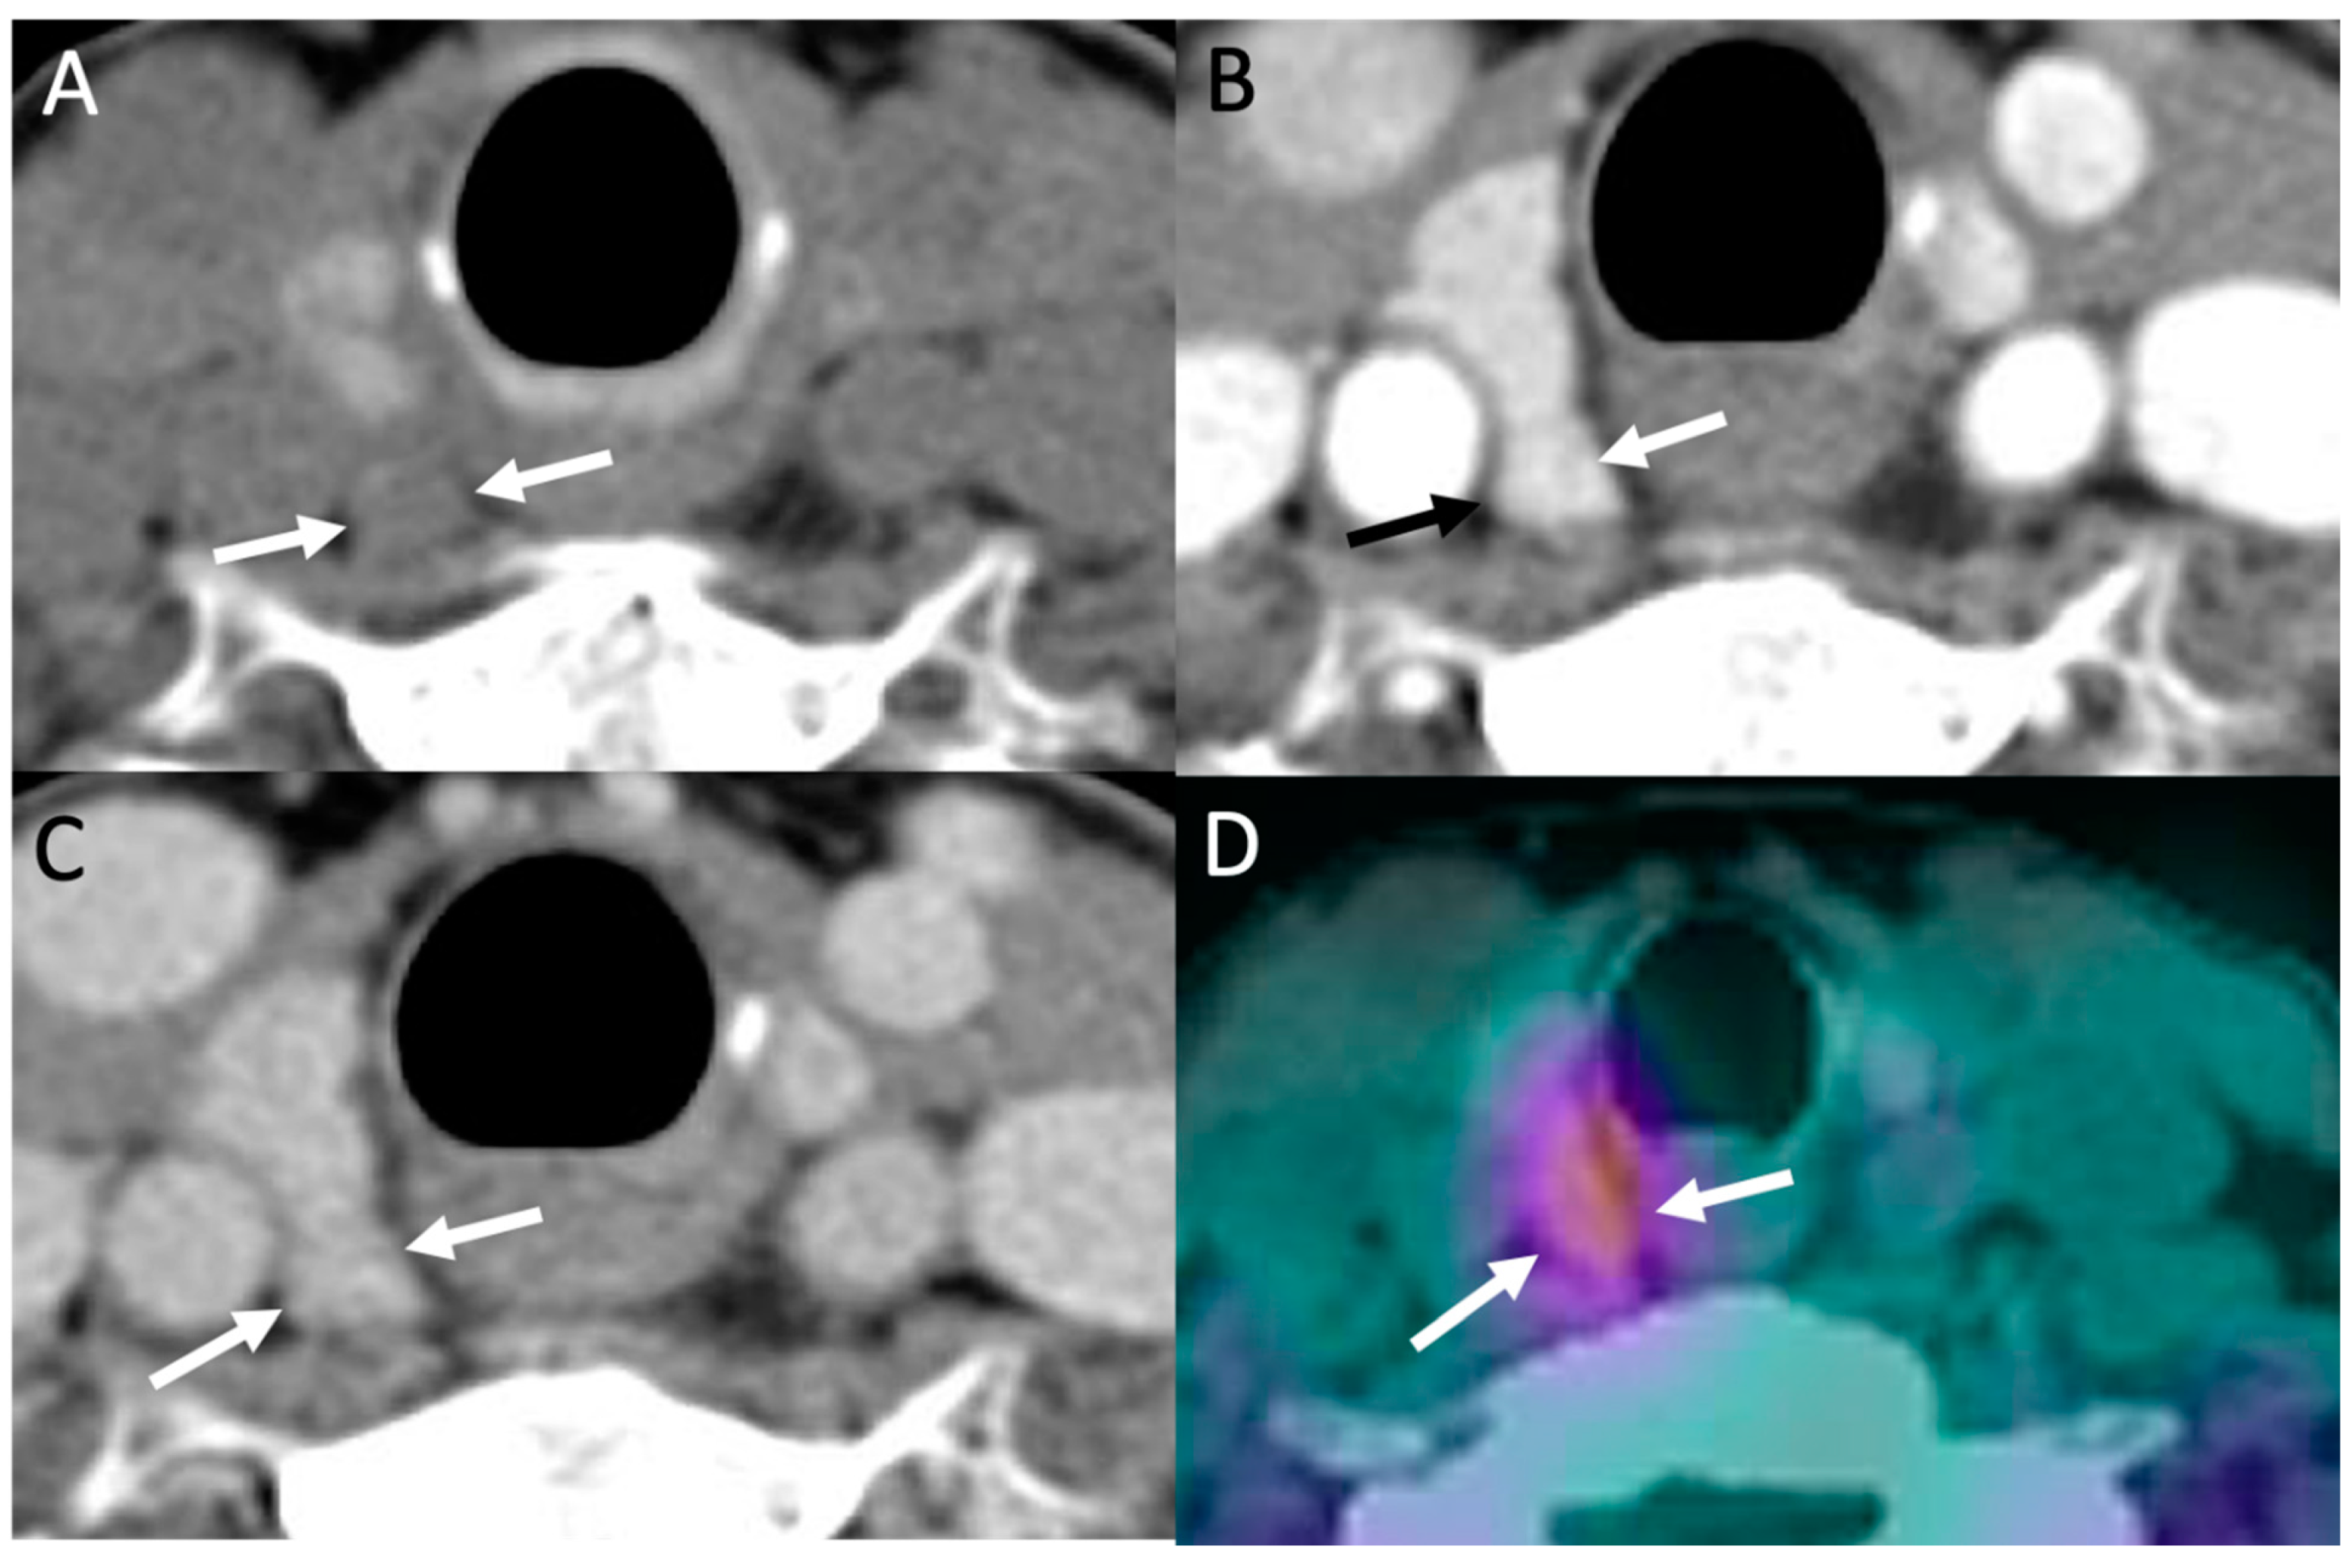

Despite its high-tech name, 4D-CT is simply a triple-phase CT of the neck and upper chest, with CT acquisitions obtained in noncontrast, arterial, and delayed phases, similar to that of triple-phase CTs of other body areas (i.e., CT of the liver). Regarding the four dimensions (“4D”), the first three dimensions refers to the three anatomic body planes of CT images (axial, coronal, and sagittal), with the fourth dimension referring to contrast enhancement over time on serial phases. Classically, a parathyroid adenoma or hyperplastic gland will demonstrate low density on noncontrast images compared to the thyroid, which is hyperdense due to high iodine content, intense enhancement on arterial phase, and rapid washout on delayed phase (Figure 4) [13]. Conversely, lymph nodes, a common mimicker of parathyroid glands, will show milder enhancement on arterial phase, which continues to slightly increase or plateau on delayed phase [13,20]. Interestingly, the aforementioned classic enhancement pattern of parathyroid adenomas is actually less common compared to other variant patterns [47], even though it is still the most commonly described pattern in the literature.

Figure 4.

Parathyroid 4D-CT: 49-year-old female with PHPT. Parathyroid 4D-CT images in noncontrast (A), arterial (B) and delayed (C) phases demonstrating a low-density nodule (arrows) posterior to the mid right thyroid gland with avid contrast enhancement on arterial phase and washout on delayed phase, consistent with right upper parathyroid adenoma. (D) Sestamibi SPECT/CT performed the same day shows corresponding focal radiotracer uptake in the adenoma (arrows).